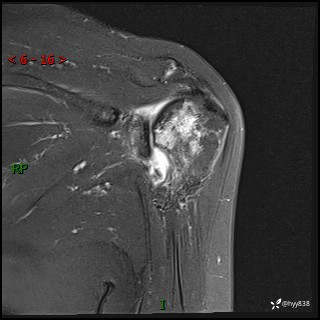

现病史:患者1月前无明显诱因出现左肩关节疼痛,于2024.07.31就诊于我院骨科门诊完善左肩关节MR:左肱骨头信号异常,肿瘤?建议进一步检查。左肩关节积液。左腋窝淋巴结增大。今为求明确诊断就诊我科,门诊以“骨质破坏”收入我科。 起病以来,精神食欲睡眠尚可,大小便正常,体力体重无明显变化。

肱骨MRI平扫(axi T1WI+cor T2WI-fs)+CE-fs(COR+SAG)